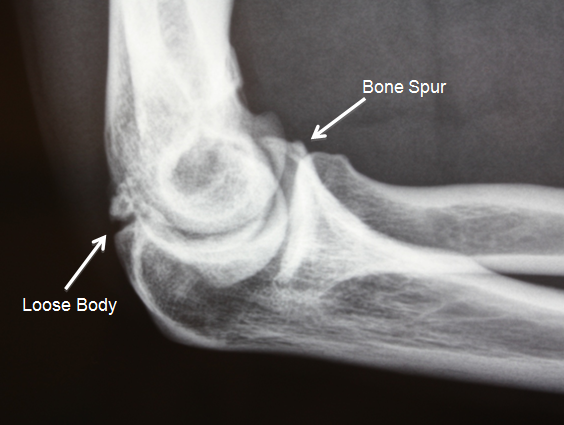

Elbow bone spur treatment. Bone spurs can cause problems if they break off and lodge in the joint. Physical therapy to improve joint strength and increase movement. Initial treatment is designed to decrease inflammation and avoid re-injury when possible.

Osteophytes do not usually cause pain but the associated arthritis might. Elbow bone spurs are common in pitchers and other throwing athletes as well as those with elbow arthritis. Ice and anti-inflammatory medications are commonly used depending on the location of the spur.

Non-operative Elbow Spur Treatment. It contains beneficial fatty acids MCTs that help with the absorption of. Physical therapy to improve joint strength and increase movement. If these treatments dont work or the bone spur affects your movement you might need surgery to remove the extra bone. This procedure involves the surgical removal of any abnormal bony growth in. If you notice symptoms suggestive of a bone spur talk to your doctor about treatment. Elbow loose bodies or spurs are best diagnosed by a physical examination by an orthopaedist.